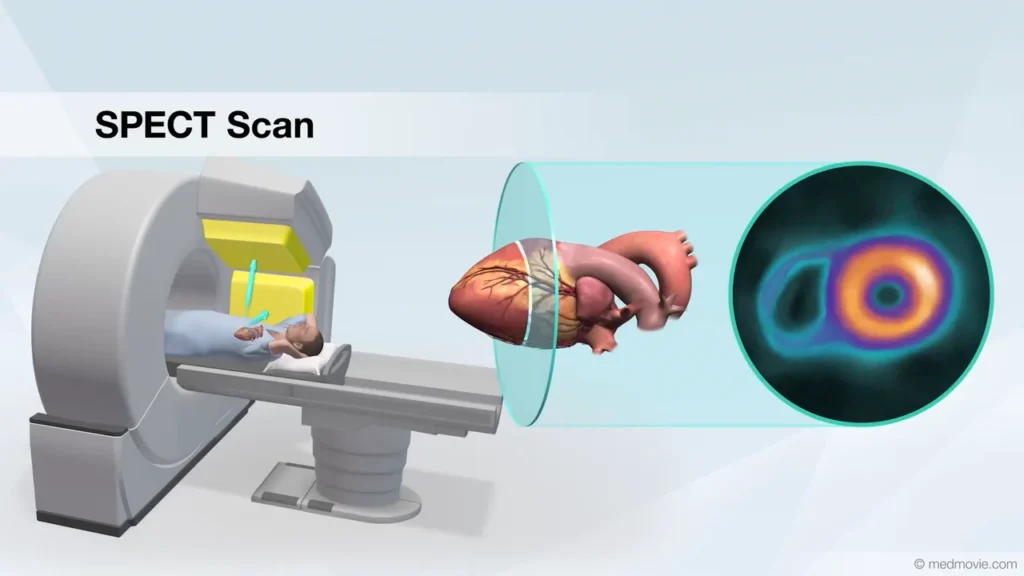

Understanding Cardiac SPECT

Myocardial Perfusion Imaging (MPI) is a non-invasive procedure utilized to assess significant coronary artery disease (CAD). This diagnostic and prognostic examination determines the extent and location of impaired blood flow to the heart, as well as evaluates pumping function and the presence of scarred heart tissue. A small amount of radiotracer is injected intravenously during both resting and stress states, achieved through physical exertion (such as treadmill exercise) or pharmacological stress. Throughout the procedure, blood pressure and electrocardiogram monitoring are conducted. Healthy heart muscle, receiving adequate blood flow, will accumulate more of the radiotracer compared to regions supplied by diseased coronary arteries.

MPI stands as the most prevalent nuclear imaging study in the US, with approximately 10 million procedures conducted annually. It’s deemed the preferred test for evaluating intermediate-risk CAD patients before considering angiography, endorsed by esteemed societies like the American College of Cardiology Foundation, American Society of Nuclear Cardiology, American Heart Association, and others.At NewMedd Diagnostics, we utilize a dual-head gamma camera for rapid acquisition, ensuring patient comfort and minimizing motion artifacts. Advanced software tools like xeleris and Emory Cardiac ToolBox enable us to obtain three-dimensional heart images, depicting stress and resting blood flow. Quantitative parametric assessment and scoring enhance interpretation accuracy.